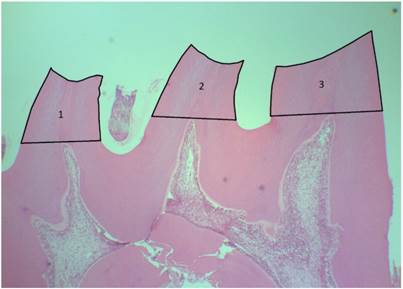

Individual cusp base areas were measured by tracing the outline of the cusp, following the occlusal surface to the tangential line cross the highest point of the pulp horn (Figure 2). The cusps that had unclear or damaged outline were excluded.

Figure 2

Area measurements procedure (1 - distal cusp; 2 - central cusp; 3 - mesial cusp). HE40x